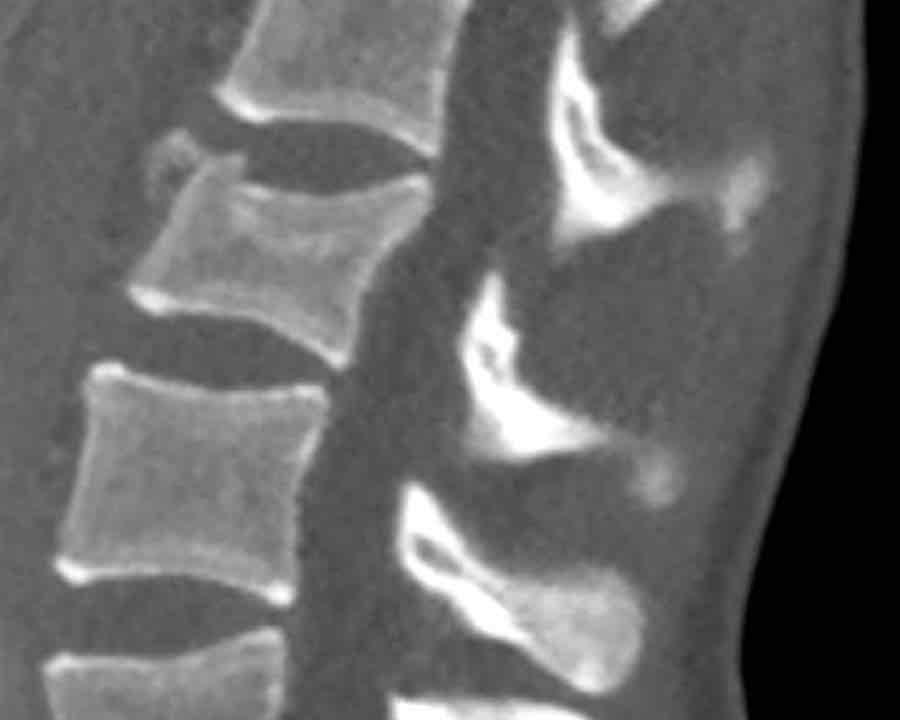

Findings

- Clear widening of the interspinous distance (yellow arrow)

- Black arrowhead: small avulsion fracture to the flexion distraction

- MRI better depicts the ligamentous injury, which was suspected on CT

Conclusion

Injury type B2

- Subtle widening of the interspinous distance (white circle)

- Small avulsion fracture spinous process (yellow arrow)

- Compression fracture with involvement of one endplate and posterior wall (1+2 points)

Injury type B2 + A3